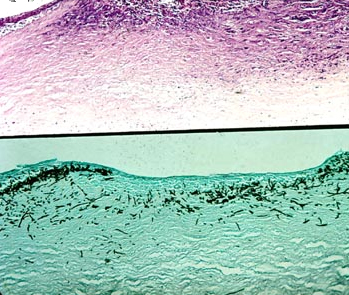

诊断:角膜溃疡(霉菌)

注释:组织切片显示溃疡形成,深层炎症反应。真菌染色显示菌丝深入基质层。

分类:角膜炎症